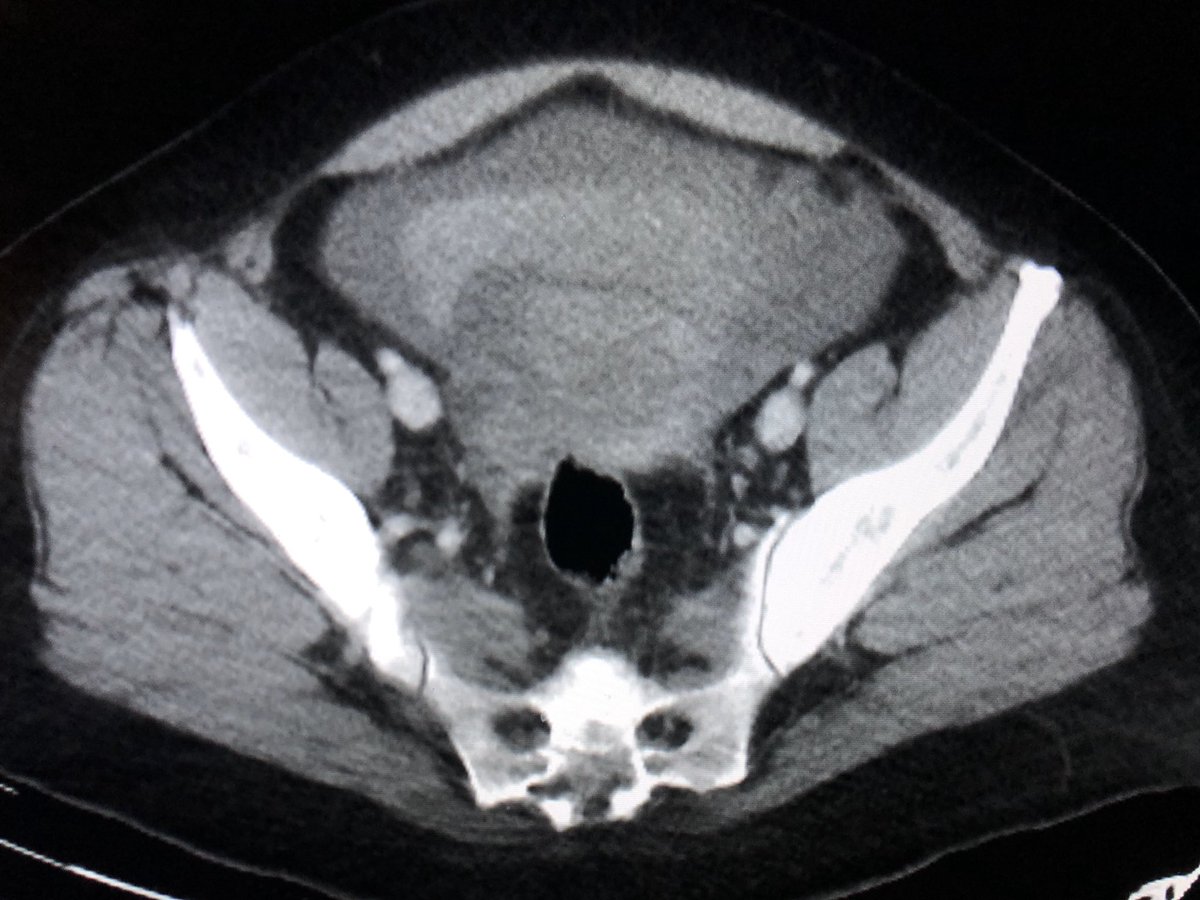

Classic! Care to guess what this appearance is pathognomic of?pic.twitter.com/11wHLxGGdr